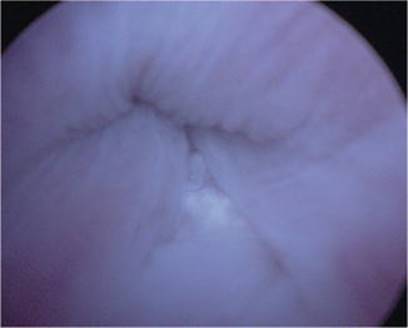

Cystoscopy is the diagnostic procedure of choice in evaluating men with suspected AUS erosion. It is indicated in any cases of recurrent urinary tract infections, hematuria, new onset urinary retention, pain with voiding, pain at the AUS pump, and sometimes in cases of prolonged catheterization. Erosion may be subtle with little external manifestations when the AUS has not yet become infected so sometimes one must have a very high index of suspicion whenever there is the possibility of AUS problems. Careful and systematic cystourethroscopy must be performed as some erosions can be very subtle. We perform urethroscopy up to the closed AUS cuff and cycle the cuff under direct vision with full flow of the irrigation in order to aid in the complete evaluation of the site (Fig. 9.2).

Fig. 9.2

(a) Eroded closed AUS. (b) Eroded open AUS